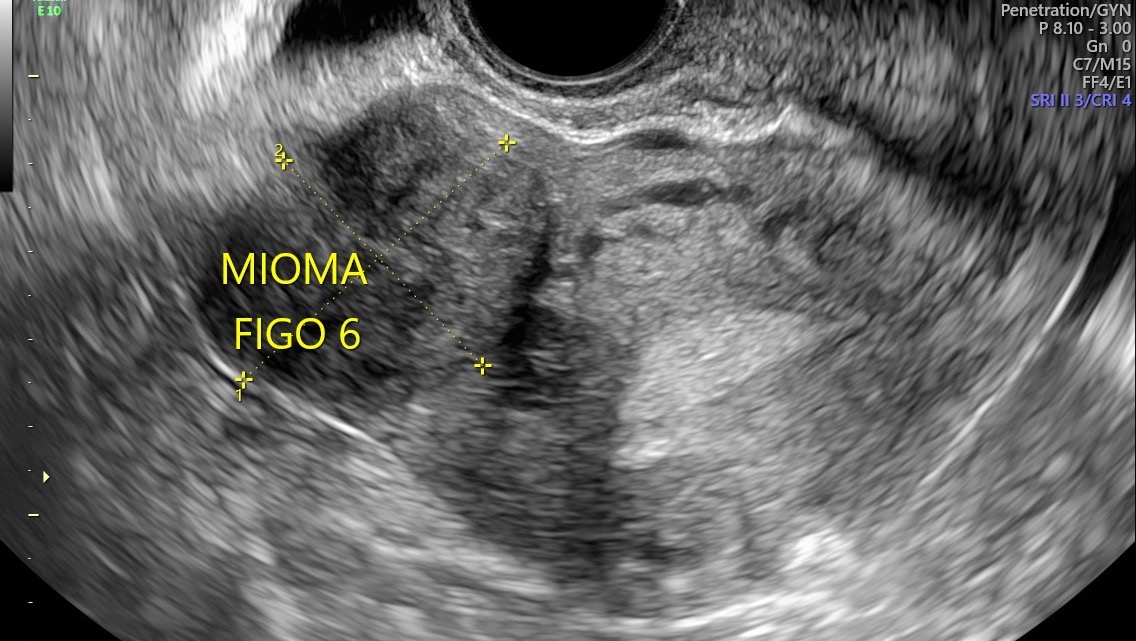

I was recently diagnosed with 16 large uterine fibroid tumors (myomas). My doctors have told me that I need immediate major surgery to remove them. The procedure I will undergo is an Open Abdominal Myomectomy, along with a biopsy to ensure there are no cancerous cells. I will also need to stay in the hospital for approximately five days during recovery. Although even if the tumors are benign, they are putting extreme pressure on my surrounding organs causing significant pain, bleeding, fatigue, and health related issues on a daily basis.

Recientemente me diagnosticaron 16 tumores de fibromas uterinos (miomas). Mis médicos me han informado que necesito una cirugía mayor inmediata. El procedimiento al que me someteré es una miomectomía abdominal abierta, junto con una biopsia para asegurar que no haya células cancerosas. También necesitaré permanecer en el hospital aproximadamente cinco días durante la recuperación. Aunque los tumores de miomas parecen ser benignos, están ejerciendo una presión extrema sobre mis órganos que los rodean, causando dolor significativo, sangrado, fatiga y problemas de salud a diario.